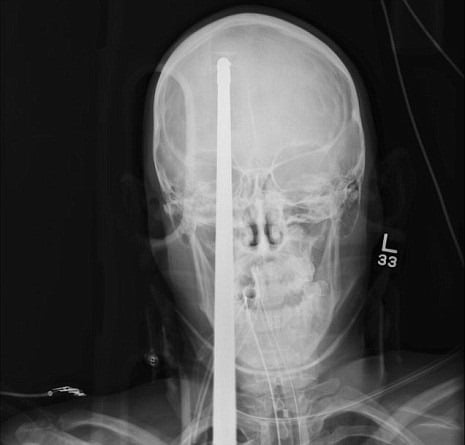

Um garoto de 16 anos Yasser Lopez de alguma forma conseguiu sobreviver a uma lança de 3 metros que entrou em sua cabeça.

O acidente aconteceu quando um arpão foi disparado por engano ao ser carregado, a lança maciça entrou através de seu cérebro com a extremidade saliente chegando a traseira de seu crânio.

Milagrosamente, Lopez não foi morto -. a lança não atingiu os grandes vasos sanguíneos em seu cérebro "É um milagre a lança perdeu todos os principais vasos sanguíneos do cérebro", disse o neurocirurgião Ross Bullock.

"A coisa mais importante é resistir à tentação de puxar essa coisa." Lopez vai passar várias semanas no hospital, mas deve fazer uma recuperação completa.